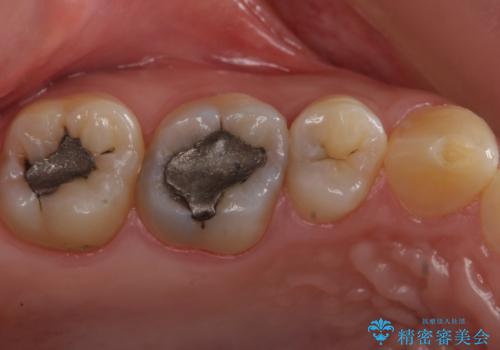

- 奥歯がしみるとのことで来院。

検査の結果、明らかに虫歯がある歯と修復物との間に虫歯がある歯が確認されました。

2歯とも白くて適合の良いセラミックインレーでの修復をすることとなりました。